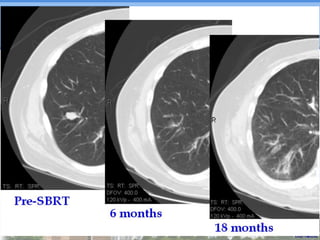

• SBRT to lung cancer at SMC:

– High local control (90%)

– Favorable 5 year survival (primary/metastatic –

66.4%/53.8%)

– Very low risk of complication (Grade 2/3 –

3.4%/1.7%)

– Highly effective and curative modality to patients

who are unfit for surgery.

Acta Oncologica, 2012

Summary

• SBRT for single or oligo-metastasis seems

quite effective and safe.

• Tumor size, disease-free interval, and presence

of extrathoracic disease are prognosticators for

survival.